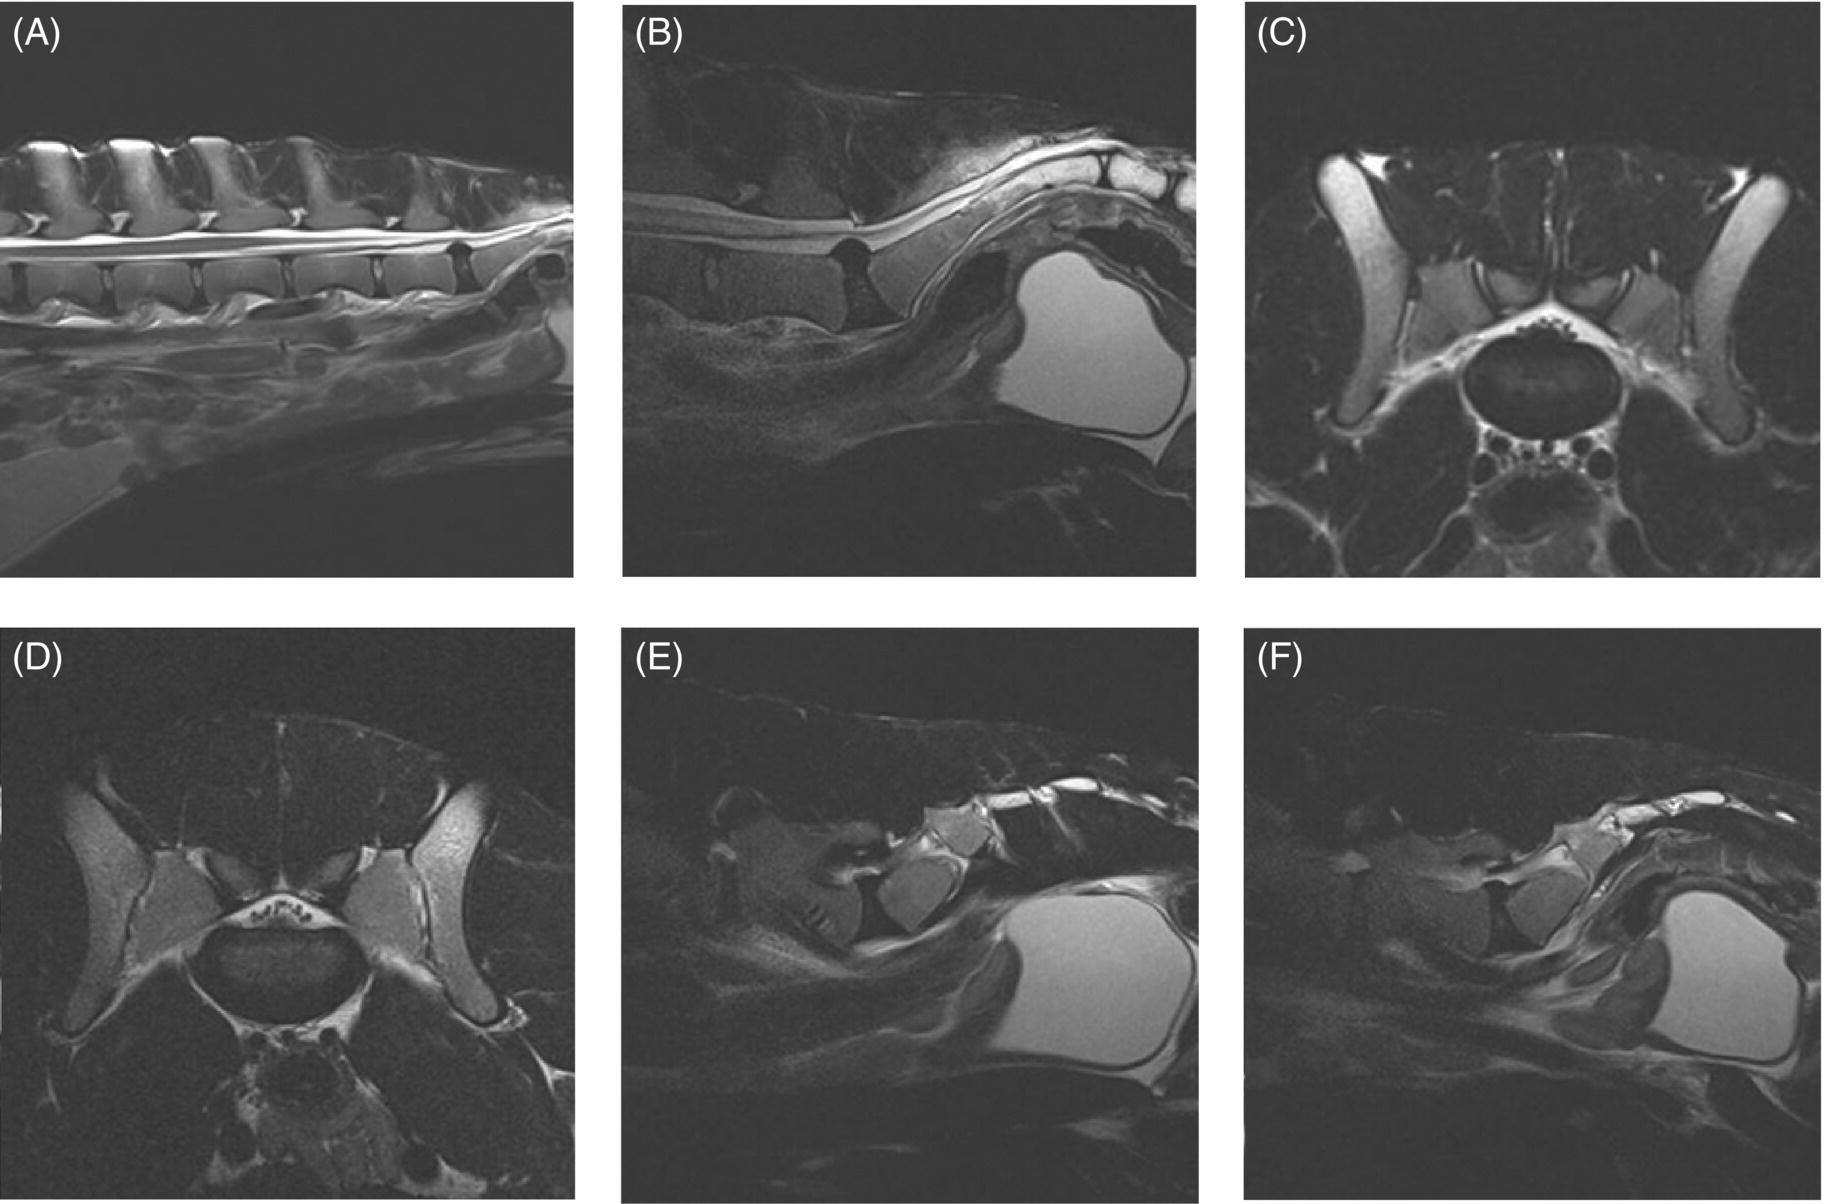

From www.researchgate.net

Canine lumbosacral spine segment in a dog with degenerative lumbosacral Lumbosacral In Dogs The lower spine is the area that is most affected. Lumbosacral disease is also known as cauda equina syndrome. Large breeds of dogs are more commonly affected with lumbosacral stenosis, and german shepherd dogs and border collies appear to be particularly prone to the condition. Degenerative lumbosacral stenosis (dlss) is the most common cause of compression of the cauda equina. Lumbosacral In Dogs.

From www.semanticscholar.org

Figure 6 from Degenerative lumbosacral stenosis in dogs. Semantic Scholar Lumbosacral In Dogs Lumbosacral disease is also known as cauda equina syndrome. The average age of onset is. Back pain is the most common sign of this condition in pets, although. The most common symptom of lumbosacral stenosis is pain. The lower spine is the area that is most affected. Large breeds of dogs are more commonly affected with lumbosacral stenosis, and german. Lumbosacral In Dogs.